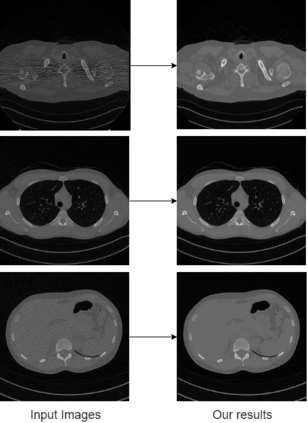

In this work, we present Eformer - Edge enhancement based transformer, a novel architecture that builds an encoder-decoder network using transformer blocks for medical image denoising. Non-overlapping window-based self-attention is used in the transformer block that reduces computational requirements. This work further incorporates learnable Sobel-Feldman operators to enhance edges in the image and propose an effective way to concatenate them in the intermediate layers of our architecture. The experimental analysis is conducted by comparing deterministic learning and residual learning for the task of medical image denoising. To defend the effectiveness of our approach, our model is evaluated on the AAPM-Mayo Clinic Low-Dose CT Grand Challenge Dataset and achieves state-of-the-art performance, $i.e.$, 43.487 PSNR, 0.0067 RMSE, and 0.9861 SSIM. We believe that our work will encourage more research in transformer-based architectures for medical image denoising using residual learning.